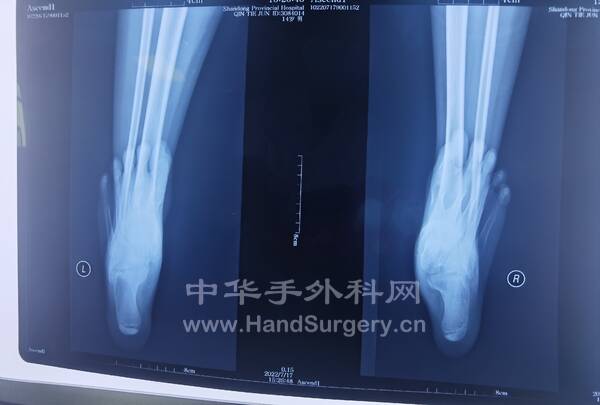

11岁男孩,双足扁平足,在老师这里见过的比较严重的孩子,老师建议手术治疗!

IMG_20220807_152904.jpg

IMG_20220807_112458.jpg